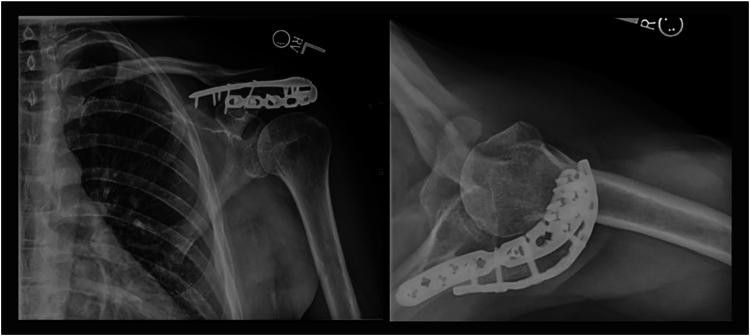

Acromion fracture associated with traumatic first time anterior shoulder dislocation: a case report.

JSES Rev Rep Tech. 2023 Dec 16;4(2):284-290. doi: 10.1016/j.xrrt.2023.11.002. eCollection 2024 May.

Acromion fracture associated with traumatic first time anterior shoulder dislocation: a case report.首次创伤性肩关节前脱位伴肩峰骨折:一例报告